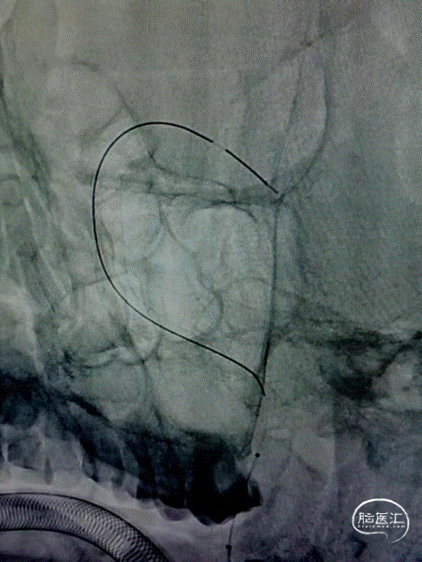

路图下支架微导管在微导丝引导下超选置于左侧大脑后动脉P2段,顺利建立通路,置入Nuva®血流导向密网支架。远端定位在动脉瘤中心以远25mm,近端定位在左侧椎动脉V4段拐弯处。